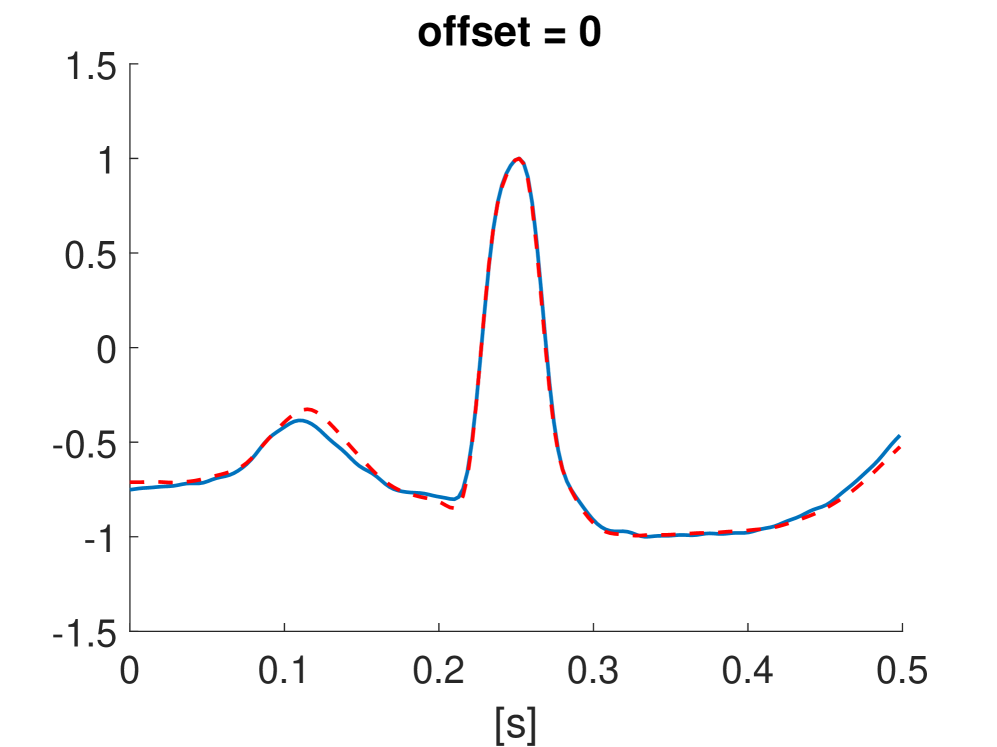

Fig. 10 shows the result in input space of moving along the first principal components in the latent feature space. As original base point we take a normal beat signal, i.e. corresponding to a hidden unit on the bottom right of Fig. 9(a). The smooth transition between the beat patterns allows for interpretation of the first principal components. This allows a clinical expert to understand on what basis the paced beats are separated by the principal components and if this basis has a physiological meaning. In order to investigate the separated region of the latent space at the top of Fig. 9(b) we start from a paced beat pattern and vary along the third principal component. This allows us to see which sort of heartbeat patterns are responsible for this specific distribution in the latent space.